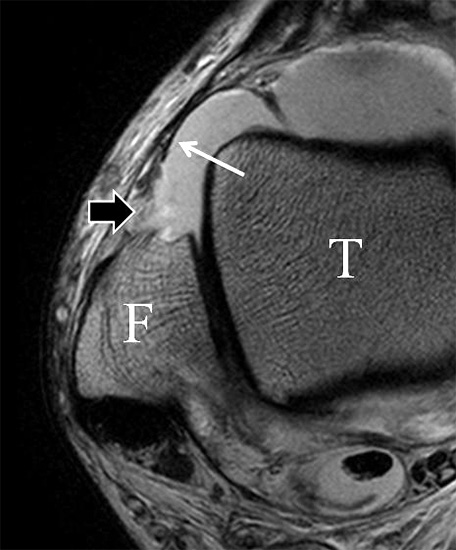

Der Ursprung des Ligamentum fibulocalcaneare liegt unmittelbar kaudal und dorsal des Ursprungs des Ligamentum fibulotalare anterius, so dass gehäuft kombinierte Verletzungen und auch ein gemeinsamer knöcherner Ausriss beobachtet werden. Nach kaudal dorsal verläuft das Band dann nach medial konvex unter die Peroneussehnen. Danach ist ein schräg deszendierender, gestreckter Verlauf bis zum calcanearen Ansatz abgrenzbar (Abb. 10). Dieser zu allen drei Standardebenen schräge Verlauf erschwert häufig die Diagnostik des LFC vor allem bei subtileren Verletzungen. Spezialprojektionen, die dem Bandverlauf orthograd folgen (entweder schräg coronar oder schräg sagittal) erleichtern auch hier die Diagnostik (Abb. 11) insbesondere nicht dislozierter Avulsionen. Assoziierte Verletzungen der Peroneussehnenloge müssen mit beurteilt werden, wobei neben Verletzungen der Sehnen und Sehnenscheiden die Beurteilung des Retinaculum peroneum superius und inferius wichtig ist. In einem Kollektiv von Patienten mit chronischen Außenbandinstabilitäten weisen 50% der Patienten eine Verletzung dieser Strukturen auf 5. Auch hier erleichtern hochauflösende Techniken die Diagnostik (Abb. 12).